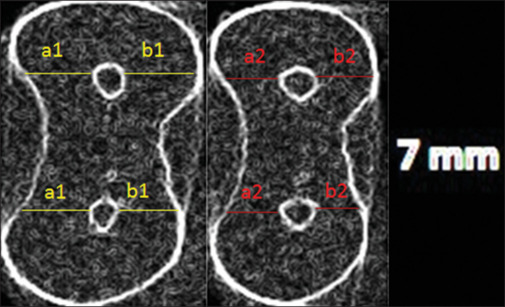

Materials and methods: In this in vitro experimental study, 60 mesiobuccal and mesiolingual canals of the mandibular first molars with a minimum length of 19 mm and 25°-40° curvature were randomly divided into three groups (n = 20) for root canal preparation with One Curve, HyFlex EDM, and EdgeFile X1. After access cavity preparation and confirming the glide path, the baseline micro-computed tomography (micro-CT) scans were obtained, and the root canals were instrumented with the respective systems according to the manufacturers' instructions. Apical transportation and centering ability were assessed at 1, 3, 5, and 7 mm from the apex by comparing pre- and postinstrumentation micro-CT scans. One-way ANOVA, independent t-test, and Duncan's post hoc test were used to statistically compare the groups, and data were analyzed by SPSS version 24 (alpha = 0.05).

Results: The three groups were not significantly different regarding apical transportation at 5 and 7 mm from the apex (P > 0.05). At 1 mm level, One Curve caused significantly lower apical transportation; while, at 3 mm level, HyFlex EDM resulted in significantly higher apical transportation (P < 0.05). No significant difference was noted in the centering ability of the three groups at 1, 3, and 5 mm from the apex (P > 0.05). At 7 mm level, EdgeFile X1 showed significantly lower centering ability (P < 0.05).